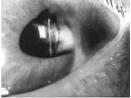

Este Cmap, tiene información relacionada con: AFAQUIA-LUIS EDUARDO, AFAQUIA QUE ES FALTA DE CRISTALINO, AFAQUIA SIGNOS SI SOLO ES UN OJO, FALTA DE CRISTALINO QUE ES EL CRISTALINO LENTE INTRAOCULAR, FALTA DE CRISTALINO DONDE ESTA ANTERIOR AL HUMOR VITREO, SI SOLO ES EN UN OJO PRESENTA ANISEICONIA, SI SOLO ES EN UN OJO PRESENTA ANISOMETROPIA, FALTA DE CRISTALINO DONDE ESTA POSTERIOR A PUPILA, SI SOLO ES UN OJO PRESENTA SALTOS DE IMAGEN, LENTE ARTIFICIAL INTRAOCULAR SE LE LLAMARA PSEUDOAFAQUIA, AFAQUIA SINTOMAS SI SOLO ES EN UN OJO, AFAQUIA CAUSAS TRAUMATISMO, AFAQUIA CAUSAS CONGENITA, AFAQUIA TRATAMIENTO LENTE ARTIFICIAL INTRAOCULAR, SI SOLO ES UN OJO PRESENTA PERDIDA DE CAMPO VISUAL, LENTE INTRAOCULAR QUE HACE ENFOCA IMAGENES, AFAQUIA CAUSAS SUBLUXACION DEL CRISTALINO